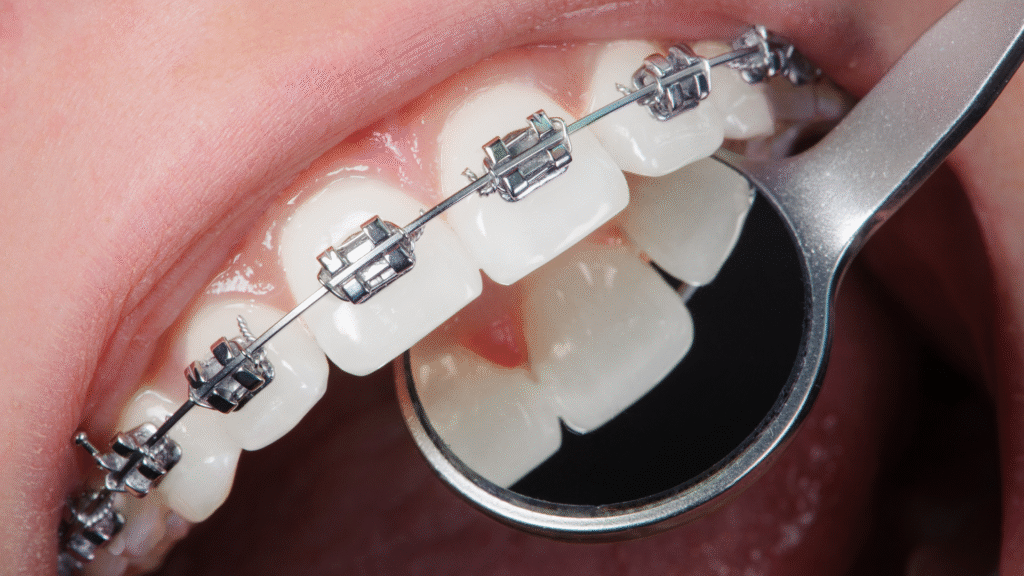

Brackets

Tratamiento de ortodoncia fijo que corrige problemas de alineación y mordida, mejorando función y estética dental.